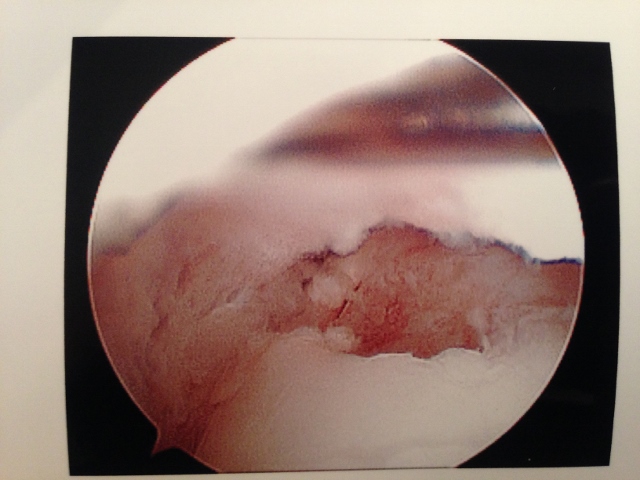

Pic of OCD after preparation and debridement .

The following pictures are debridement of damaged cartilage that is abnormal in appearance and/or loose. This is removed completely to expose the subchondral (underneath cartilage) bone plate.